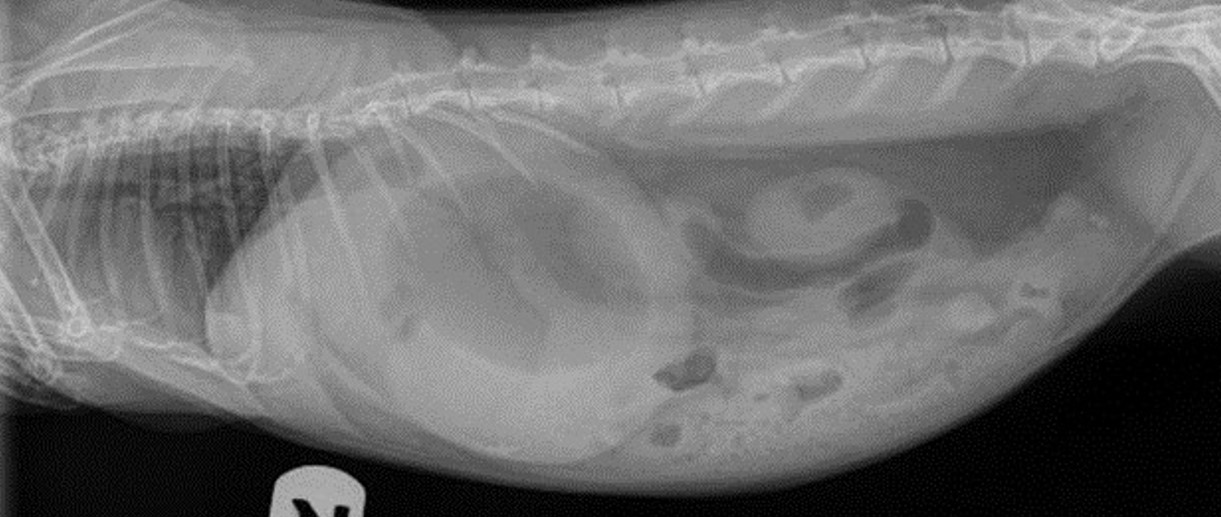

X-ray of a bloated rabbitRadiograph of a rabbit in bloat.

Photo courtesy of Dr. Sari Kanfer, Exotic Animal Veterinary Center.

An owner's first signal that something is wrong will probably be GI stasis (remember, GI stasis is a symptom). Symptoms will come on very quickly. The bunny will stop eating, and he may be sitting in a hunched position in a corner or under a box. He may show classic signs of pain - eyes narrowed, teeth grinding, flattened cheeks and a reluctance to move. The body temperature will be lower than normal. The biggest bloat clue for the owner is in the stomach and abdomen area. In a bloated rabbit the stomach may be enlarged and feel firm to the touch. It can feel very much like a watermelon or a water balloon. This is because  the build-up of fluid and gas happens in an area closest to the obstruction. Note that if the obstruction is not near the stomach, but further down the GI tract, it might be harder for the average owner to feel any dilation. It's important to know that in the earlier stages, the stomach may look only mildly distended and may not feel unusually hard to the touch. However x-rays will show a typical gas pattern.

Veterinarians have a more precise way of diagnosing an obstruction. They are better at palpating the abdominal area than the average owner, and can estimate where the source of the obstruction lies. X-rays and ultrasound of the abdominal area may give details such as the precise location of the obstruction, the presence of gas, liquid, etc. However, if the patient is not stable enough for sedation, x-rays may not be done until later.

X-ray of bloat with 4 hours of treatmentThe photos on the left side (top and bottom) show the gas patterns and the size of the stomach at the beginning of treatment. On the right side (top and bottom) the images show what the stomach and intestines look after 4 hours of treatment.

Photos courtesy of Dr. Sari Kanfer Exotic Animal Veterinary Center.

Multiple x-rays will track the movement of the obstruction. The gas patterns should shift further down the intestines if medical treatment is working and the obstruction is making its way out. If movement is not seen, surgery may be advised as it suggests that the obstruction is either stuck or there may be some external factor such as a tumor, abscess or adhesion present.